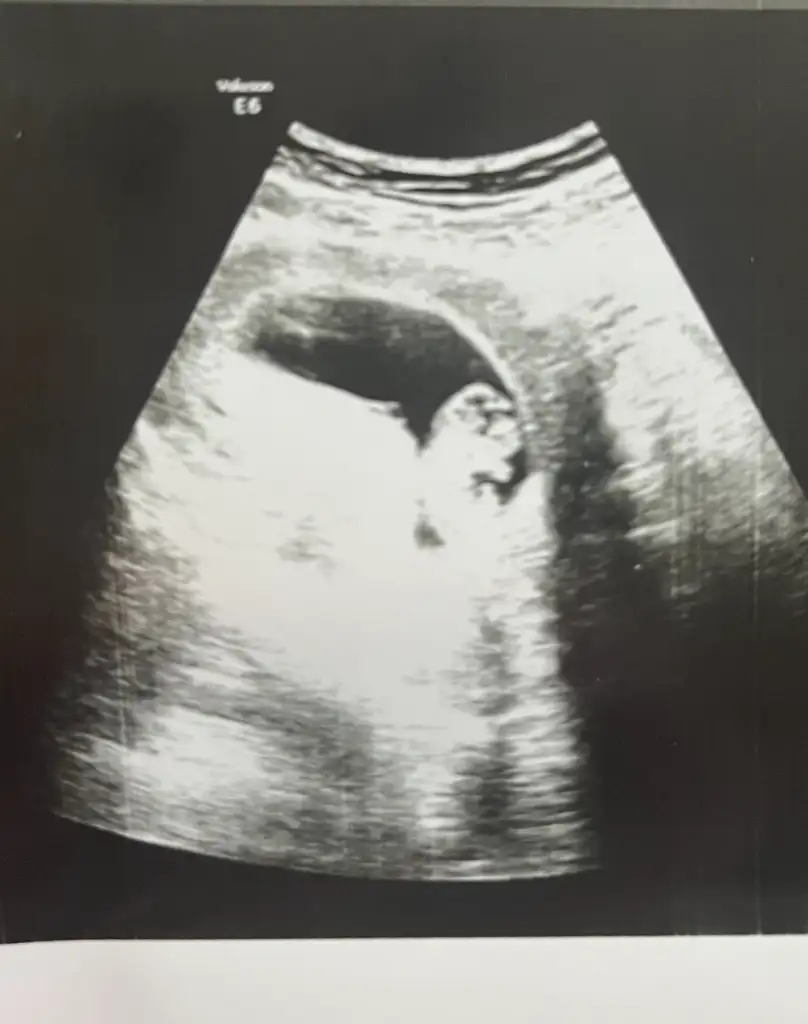

maşallahhhKızlar bugün kontrolüm vardı çok şükür her şey yolundaYakın zamanda kontrole gitmediyseniz bebişler çok büyümüş haberiniz olsun Ellerini kollarını görebiliyorsunuz. Fetal Dna için Natera ile çalışıyormuş doktorumun kliniği. Amerika’ya gönderen bir firma anladığım kadarıyla. Yarın arayıp ayrıntılı bilgi ve fiyat bilgisi alacağım size de haber veririm.

Ayy hayırlı olsun canımKızlar bir erkek haberi de benden gelsin. 12+1 im normalde, ultrasonda 12+5 çıktım. İkili teste erkek çıktık. O kadar çok kız hissediyordum ki erkek olmasına bir tık şaşırdım. 18.haftada kesin %100 sonucu söylerim, sen yinede alışverişe başlama dedi ama yukarı doğru çıkıntı net görünüyordu. Önemli olan sağlığı. Çok şükür o da şuanlık iyi görünüyor. Darısı haber bekleyenlere

pipisi varAyy hayırlı olsun canımben de basından beri erkek hissediyorum normalde kız istiyorduk ama erkege alıstırdım kendimi nedense senin ultrason görüntün nasıldı 11.haftada acaba buna benziyor muydu çıkıntı

Eki Görüntüle 3620639